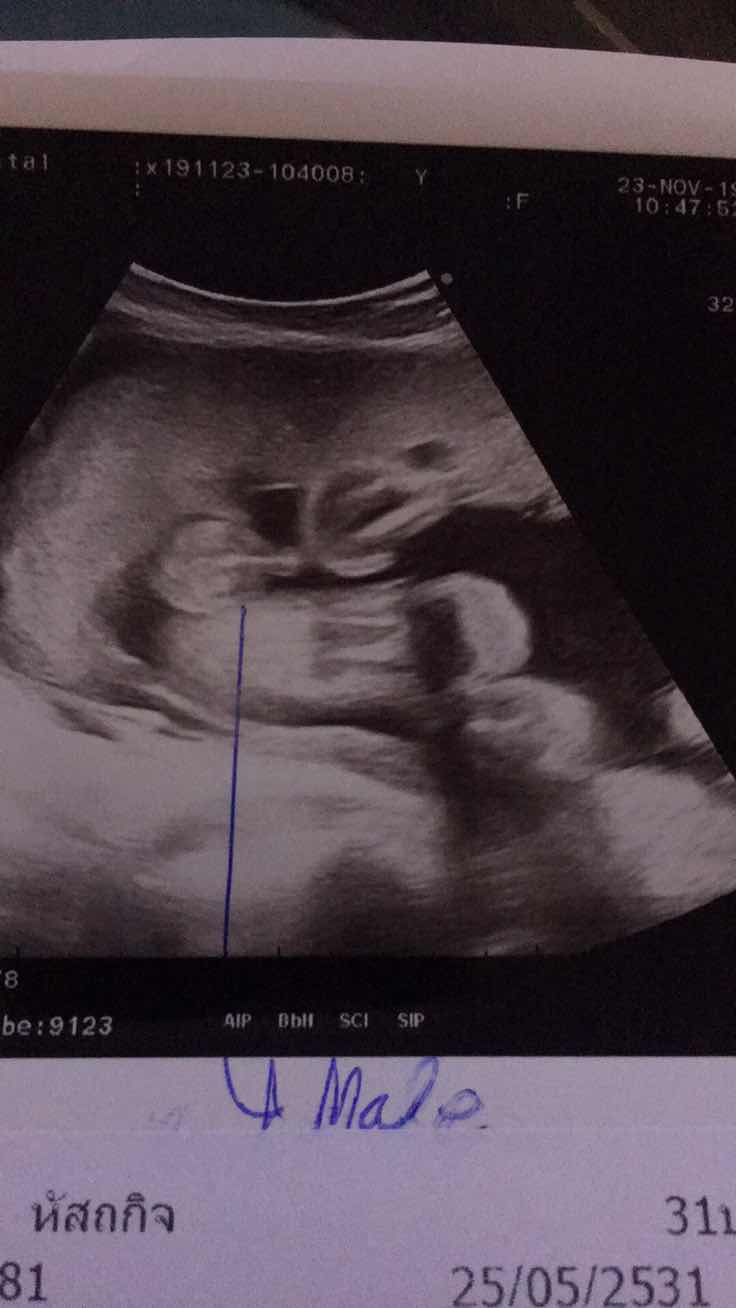

ปู้จายคร๊าบบ😆😆